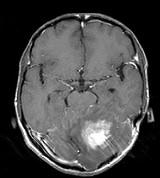

问题 男,41岁,左枕部疼痛,右侧肢体乏力,并渐进性加重半个月,右侧肢体乏力,行走不稳,请根据所提供图像,选择最可能的诊断()

选项 A.(小脑)血管母细胞瘤 B.(小脑)髓母细胞瘤 C.(小脑)炎性肉芽肿 D.(小脑)转移瘤 E.(小脑)星形胶质细胞瘤Ⅰ~Ⅱ级

答案 E